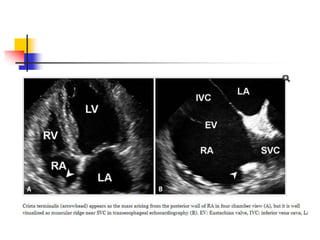

Crista Terminalis

 Crista terminalis is a well-defined fibromuscular ridge

separating a smooth sinus venarum and trabeculated

RA.

 Externally, it corresponds to the sulcus terminalis,

and internally, it extends from SVC to IVC along the

lateral RA wall.

 Embryologically, crista terminalis develops from the

septum spurium, which corresponds to the fused

boundary between embryonic sinus venosus and RA

proper.

 Prominent crista terminalis may be confused for RA

tumor on TTE.

 Echo findings s/o prominent crista terminalis instead

of tumor are as following:

 a nodular mass of similar echogenicity with adjacent

myocardium;

 the location on posterolateral wall of RA near the

SVC, which corresponds to the course of crista

terminalis connecting the SVC and IVC;

 the phasic change in size becoming thicker or larger

during atrial systole.

 Bicaval view of TEE best visualizes the crista

terminalis.